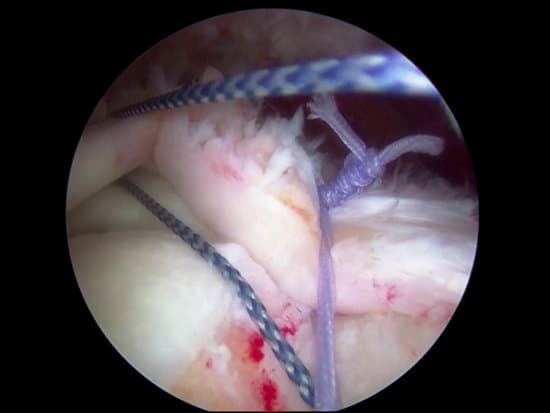

관절경 삽입: 작은 절개를 통해 **내시경(관절경)**을 삽입하여 어깨 내부를 확인합니다.

파열 복구: 파열된 힘줄을 봉합하거나 재부착하며, 심한 경우 인공 힘줄을 이식할 수 있습니다.